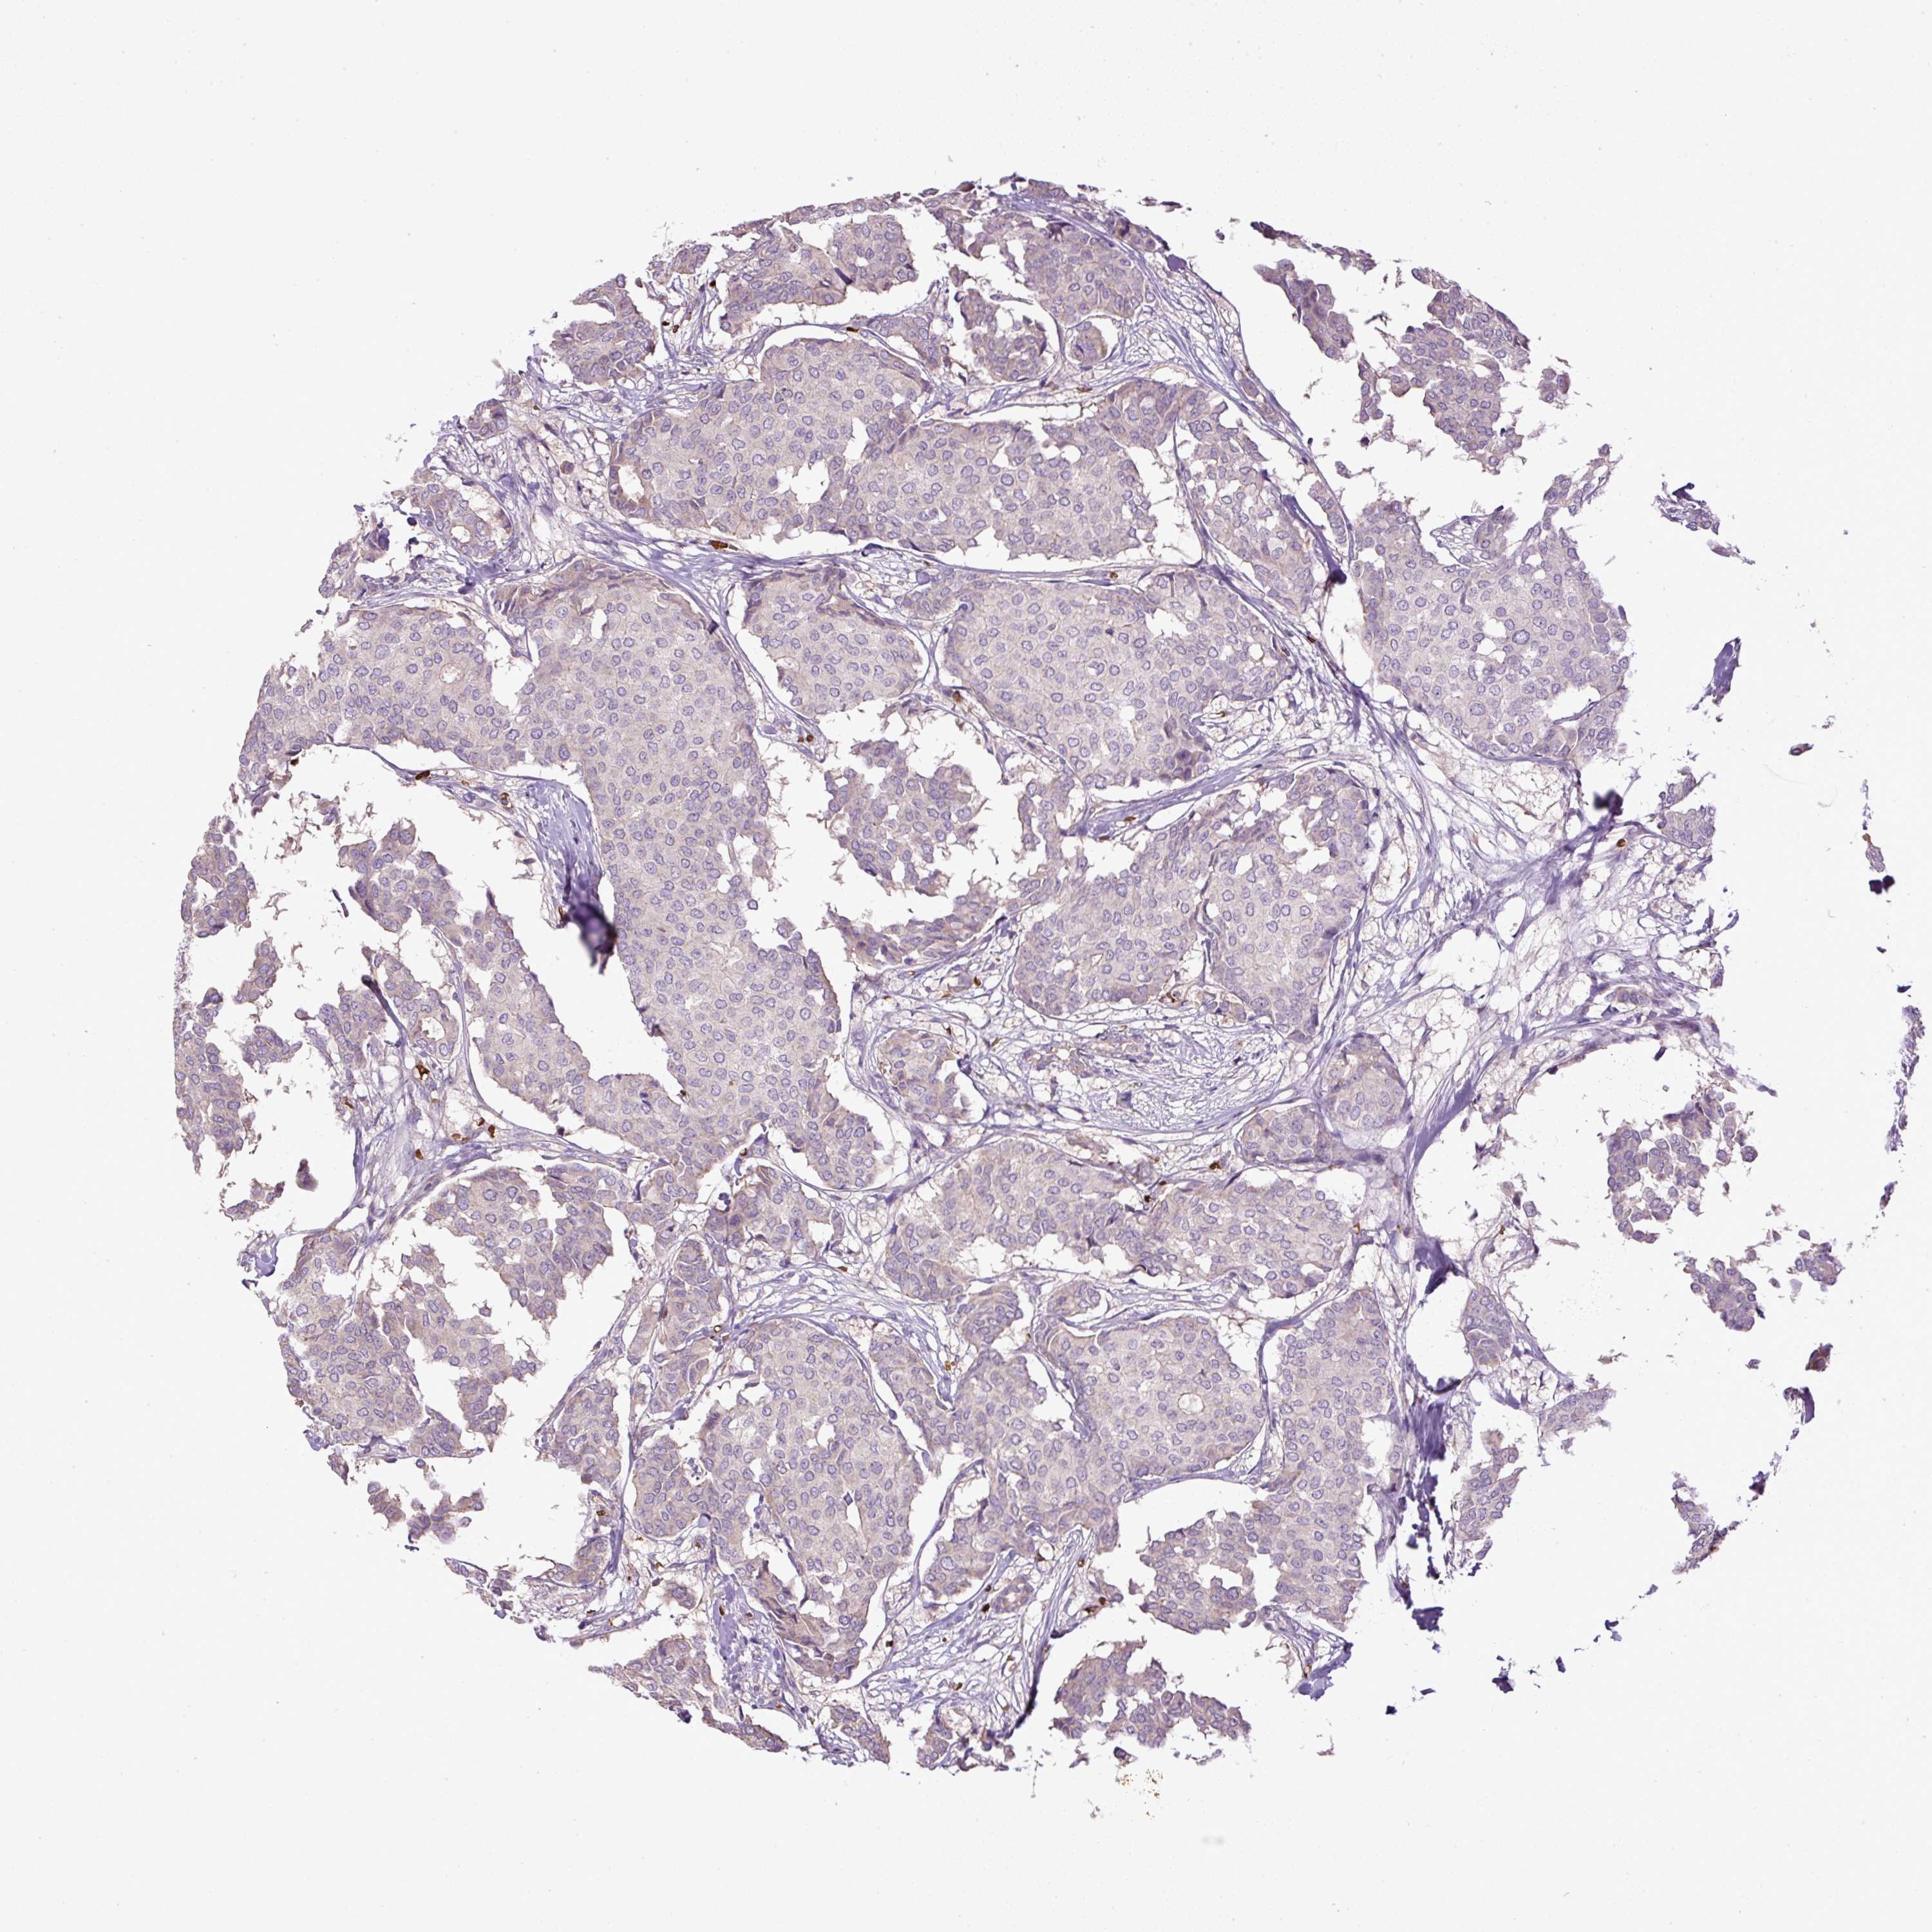

BRCA TCGA BRCA VALIDATION PROTEIN EXPRESSION